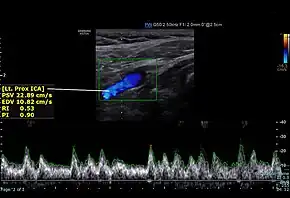

Screenshot of a normal proximal internal carotid artery spectral Doppler | |

Doppler ultrasound allows for assessment of carotid arterial blood flow. Blood flow velocity is increased in areas of stenosis compared to normal. Therefore, doppler imaging substantially aids in the diagnosis of carotid artery stenosis by ultrasound.[2] Internal carotid artery (ICA) is located posterolateral, and larger when compared to the external carotid artery (ECA). ICA has low resistive pattern (difference between the blood velocities during heart systole and diastole) when compared to ECA.[3] ICA has sudden increase in velocity of blood flow during systole and persistent forward blood flow during diastole.[5][6] ICA peak systolic velocity more than 125m/sec and diastolic velocity more than 40 m/sec signifies stenosis.[3]